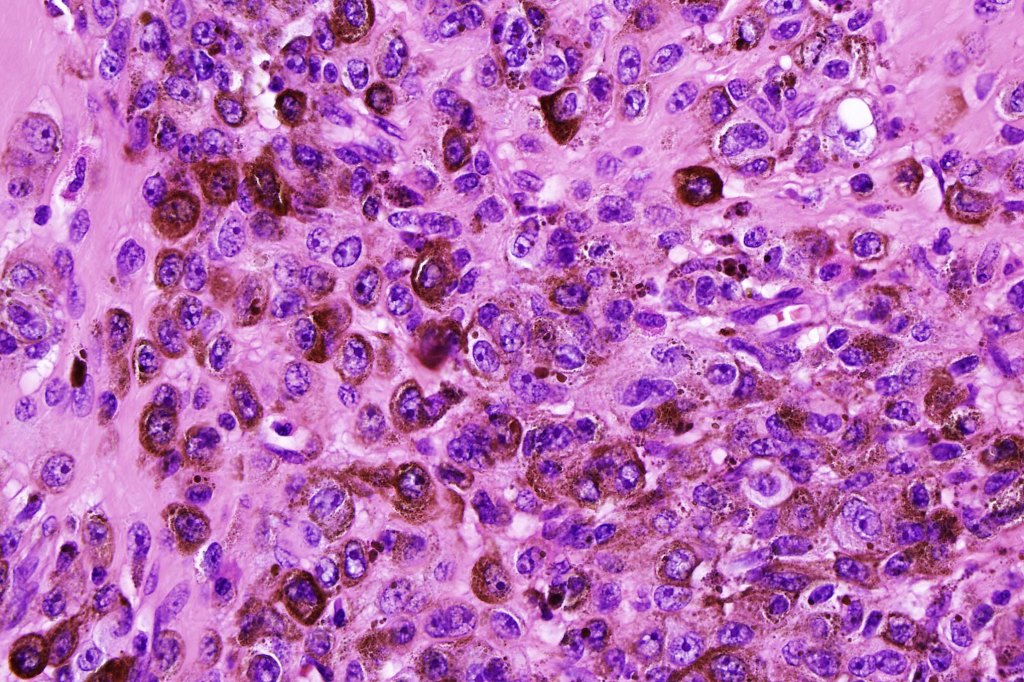

•Typical melanoma, nevoid melanoma, small cell melanoma, pleomorphic/anaplastic melanoma, melanoma with heterologous differentiation & malignant nerve sheath-like melanoma.

This melanoma arose in a small congenital nevus of the scalp. It metastasized widely. Varying features in different fields.